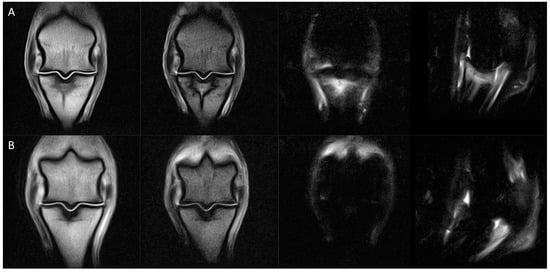

2.3. MRI Evaluation